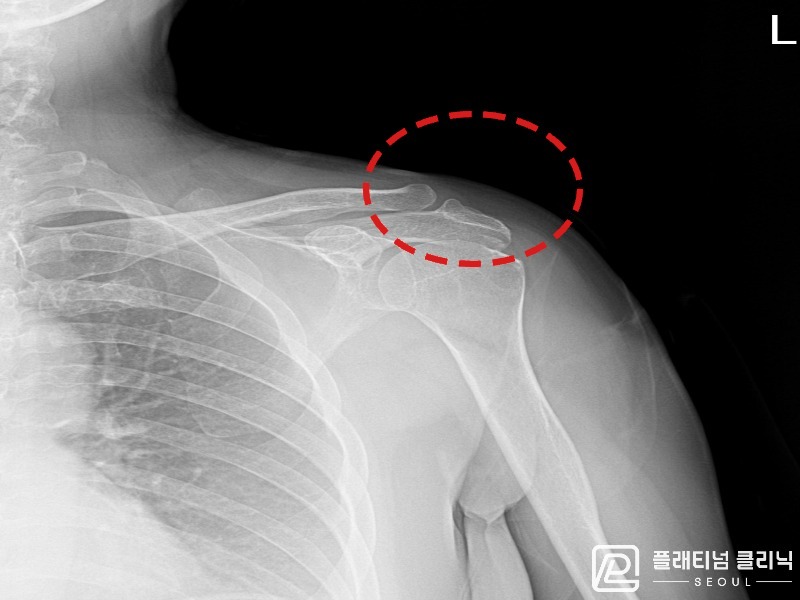

[촬영시기:21.09.02~21.10.07]

[석회분쇄흡입술] 좌측 어깨 통증으로 팔을 옆으로 올리기 어려워진 60대 남성 환자로, X-ray에서 좌측 극상근건 내 석회 침착이 확인되어 석회분쇄흡입술을 시행하였습니다.